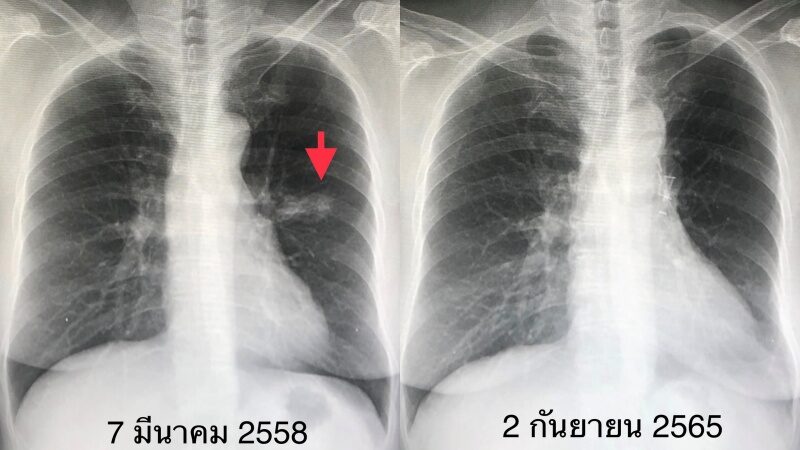

ระบุว่า "มะเร็งปอดเป็นมะเร็งที่พบบ่อย ถ้าพบเร็วในระยะแรก ระยะ 1-2 สามารถรักษาให้หายขาดได้ด้วยการผ่าตัด ผู้ป่วยหญิงอายุ 65 ปี เมื่อ 7 ปีก่อน ตรวจร่างกายประจำปี และเอกซเรย์ปอดทุกปี พบก้อนเล็ก ๆ ที่ปอดข้างซ้ายด้านบน ผ่านไป 1 ปีก้อนนี้โตขึ้น (ดูรูป) จึงมาปรึกษา"

ภาพจาก หมอมนูญ ลีเชวงวงศ์ FC

"ทำ PET scan สงสัยเนื้องอกเป็นมะเร็งปอด ไม่กระจายไปอวัยวะอื่น ส่องกล้องเข้าไปดูในหลอดลม ไม่พบอะไรผิดปกติ ได้ทำการผ่าตัดปอดโดยวิธีส่องกล้องเมื่อวันที่ 7 มีนาคม 2558 ตัดปอดกลีบบนข้างซ้ายออก และตัดชิ้นเนื้อจากต่อมน้ำเหลืองที่ขั้วปอด และรอบๆ เนื้องอก ผลพยาธิวิทยาเป็นมะเร็งปอดขนาด 4 เซนติเมตร ชนิด adenocarcinoma ยังไม่กระจายเข้าต่อมน้ำเหลือง"

"สรุป: ผู้ป่วยรายนี้ไม่มีอาการ ไม่เคยสูบบุหรี่ แต่หายใจควันธูปต่อเนื่อง เป็นมะเร็งปอดระยะ 2A ( มะเร็งปอดระยะ 2A คือมะเร็งขนาด 4-5 เซนติเมตร และไม่แพร่กระจายเข้าต่อมน้ำเหลือง หลังผ่าตัดมีโอกาสรอดชีวิตที่ 5 ปี ร้อยละ 60 ) ติดตามผู้ป่วย 7 ปีหลังผ่าตัด ไม่พบมะเร็งปอดกลับมาใหม่ ถือว่าหายขาดจากโรคนี้ (ดูรูป) ผู้ป่วยได้เลิกจุดธูปหลังผ่าตัดปอด"